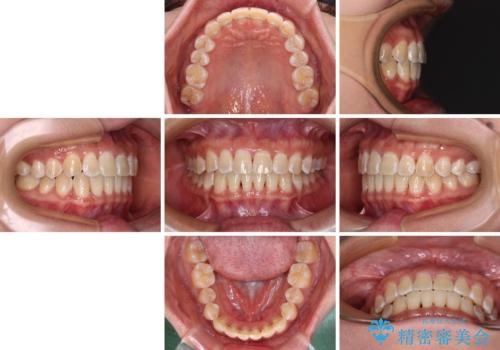

前歯の隙間と上下正中のズレを解消

- 上下前歯隙間と正中のズレを改善したいとのことで来院された患者様です。

自己管理を減らしたいとのことで、ワイヤー装置による矯正治療を行うこととしました。

正中がなかなか合わずに、2年近くの治療期間を要しました。